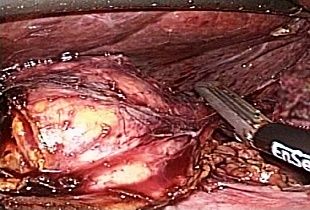

治療が必要と判断した場合には、当院では腹腔鏡下腎(尿管)悪性腫瘍手術を施行しています。